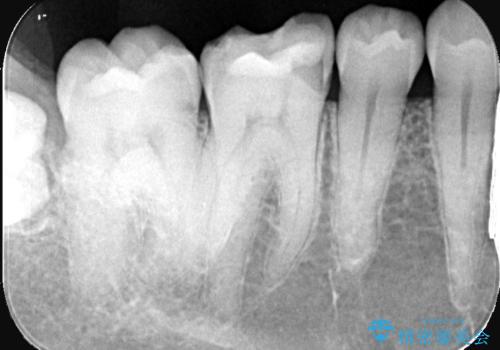

- 主訴は、歯が欠けてしみるとのことでした。欠けた部分が大きいことから、被せものでの治療をおすすめしました。

審美性の良いオールセラミッククラウンを選択されました。